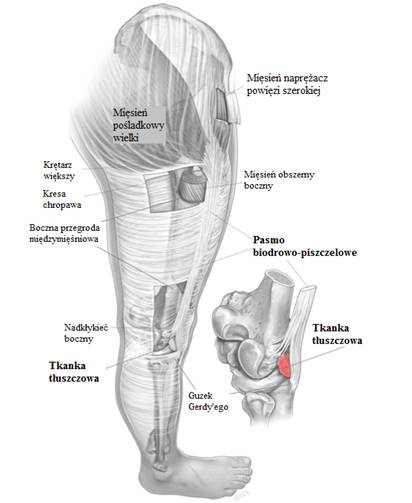

Pasmo biodrowo-piszczelowe jest pogrubieniem powięzi, która biegnie od miednicy w dół, do bocznej części kolana. Wyobraźmy sobie nogę owiniętą folią spożywczą, z grubszym pofałdowanym fragmentem znajdującym się w bocznej części. Powszechnie uważa się, że podczas zginania i prostowania kolana, pasmo biodrowo-piszczelowe ociera się o kostną wyniosłość na zewnętrznej stronie kolana (nadkłykieć boczny kości udowej), powodując zespół tarcia pasma biodrowo-piszczelowego, jak przedstawiono na ilustracji poniżej.

Dolny koniec pasma biodrowo-piszczelowego to taśma zbudowana z gęstej włóknistej tkanki łącznej, która ma kilka punktów przyczepu. Przytwierdza się do zewnętrznej części kości udowej (nadkłykieć udowy boczny), kości piszczelowej (guzek Gerdy’ego), rzepki (pasmo biodrowo-rzepkowe) i bocznych części mięśni grupy tylnej uda (miesień dwugłowy uda). Istnieje kilka warstw tkanek, ale zwykle dzieli się je na powierzchowne i głębokie warstwy, dla uproszczenia. Poniżej uwidoczniono bardziej powierzchowne warstwy.

Szerokie pasmo (A) przytwierdza się do ścięgna mięśnia czworogłowego, rzepki i ścięgna rzepki. Szeroka zbita część centralna (C) przytwierdza się do guzka Gerdy’ego i głębokiej powięzi nogi, a cienka, ale wytrzymała część rozciąga się z tyłu (P), mocując mięsień dwugłowy uda i ścięgno, głowę kości strzałkowej i głęboką powięź uda. Te punkty przyczepu współpracują ze sobą podczas zginania i prostowania, by zapewnić kompleksową stabilizację bocznej części kolana.

Głębsze włókna pasma biodrowo-piszczelowego są przytwierdzone do kłykcia bocznego za pomocą włóknistych pasemek, połączonych z powłoką silnie unerwionej tkanki tłuszczowej. Te głębsze pasma są powszechnie nazywane włóknami Kaplana i są przymocowane do wyniosłości noszącej nazwę guzka nadkłykciowego. Dzięki temu umocowaniu pasmo biodrowo-piszczelowe nie może ocierać się tam i z powrotem o guzek, co wynika ponownego przeanalizowania koncepcji tarcia jako przyczyny bólu. Przytwierdzenie zarówno do rzepki, jak i mięśnia dwugłowego uda w jeszcze większym stopniu zmniejsza ruchy przód/tył, gdy kolano się zgina i prostuje.